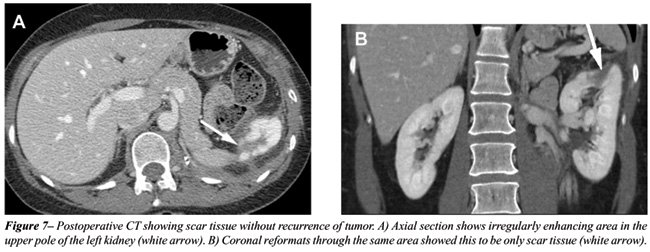

With the rapid acquisition of multiple simultaneous slices and thin-section reformatted coronal and/or sagittal images, the 64-slice CT scanner provides excellent detail in demonstrating local extension to the bowel and retroperitoneum (see Figures-2, 3, 5, 6 and 7). Multiplanar three-dimensional reconstruction techniques including volume rendering, maximum intensity projection and shaded surface display provide comprehensive information about the relationships and possible involvement of vascular structures in renal neoplasms.